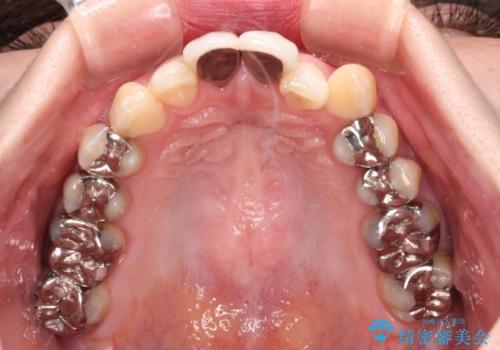

- 前歯のデコボコとセラミッククラウン周りの黒い縁を気にして来院された患者様です。

前歯の黒い縁は、矯正治療後にオールセラミッククラウンにて改善することとしましたが、いち早く目立たなくしたいとのことで、事前に矯正治療用仮歯に置き換えてから矯正治療を開始しました。